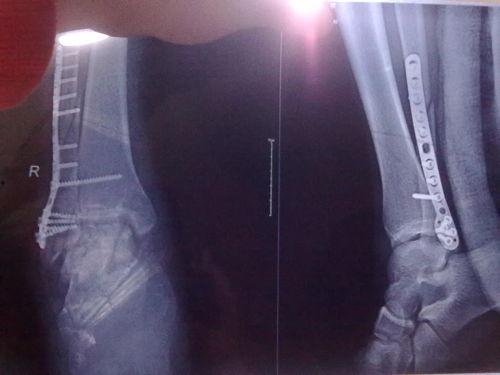

三、脚踝韧带撕裂的图片展示

下面是一些真实的脚踝韧带撕裂图片,让你直观地了解这种损伤。

1. 轻度撕裂:图片中可以看到,脚踝周围的韧带只有轻微的断裂,但仍有部分连接。

2. 中度撕裂:这种撕裂的韧带断裂面积较大,但仍有部分连接。

3. 重度撕裂:韧带完全断裂,断裂处可见明显的缝隙。

1. 诊断:医生会根据你的症状和体征进行诊断,必要时还会进行X光或MRI检查。